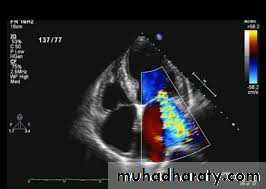

• 8. 2D Echo cardiography - valve

• edema ,mitral regurgitation, LA & LV dilatation,

• pericardial effusion,

• decreased contractility.